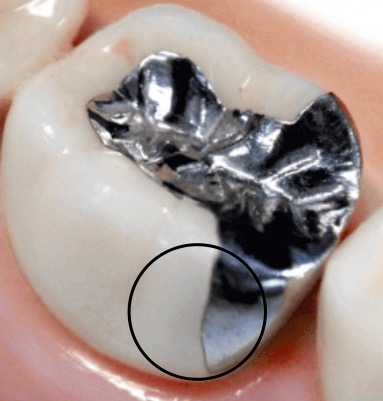

画像のような形で治療された銀歯の◯印の部分に、ざらつきを感じます。段差があるようなのですが、研磨で段差を感じないようにすることは可能でしょうか。多少の段差は仕方ないものでしょうか。また、自分の歯と複雑に詰められている(噛む面の)場合、ざらつきがないように研磨するのは難しいものでしょうか。

画像1IMG_9110.jpeg